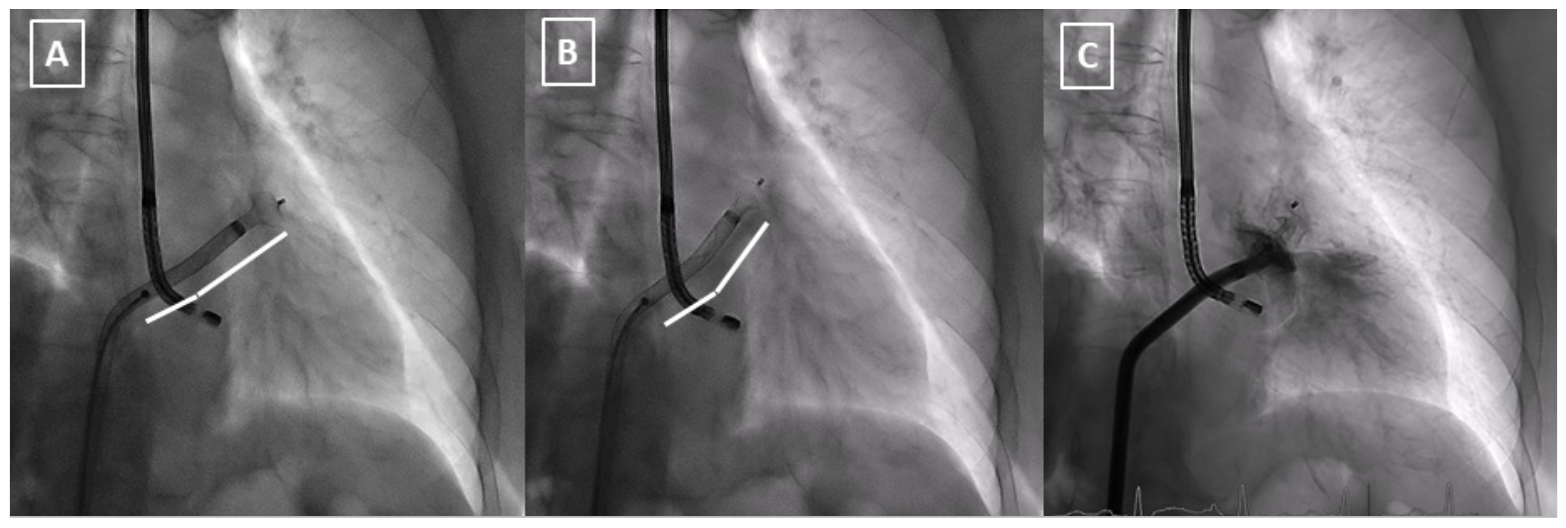

Left atrial appendage (LAA) occlusion has emerged as an alternative to oral anticoagulation in non-valvular atrial fibrillation. The success rate is high, but we are still facing some challenging LAA anatomies that may increase the risk of suboptimal results. Coaxiality between the delivery sheath and the LAA neck is therefore crucial. Nevertheless, even with an optimal transseptal puncture, some LAA morphologies imply some difficulties. The novel Amplatzer steerable delivery sheath (Abbott Cardiovascular) offers the possibility of deflecting the distal end in a wide spectrum of angles from 0º to 120º (Figure 1). This could be determinant to achieving a final coaxial position with the neck during the deployment and improving the rate of complete occlusion.

In this case, although we faced classical chicken-wing anatomy, it was difficult to achieve a coaxial angle, as we can appreciate in computed tomography and fluoroscopy during the first attempt with the conventional 45º x 45º sheath (Figures 2A, 2B). Using the steerable sheath, even with a posterior-inferior transseptal puncture, the angle was again not desirable (Figures 2C-2F). Therefore, with a slight deflection (red arrow), the coaxiality improved in a determinant way. These small variations must be done in the ball position to prevent complications. These corrections offer the possibility to achieve an optimal angle for the deployment (white lines in Figures 3A, 3B; Video Series), helping to complete the desired final position (Figure 3C).

In conclusion, the Amplatzer steerable sheath is useful for LAA occlusion, especially in cases with challenging anatomies. Small variations of the distal end angle can improve the success rate and reduce complications.